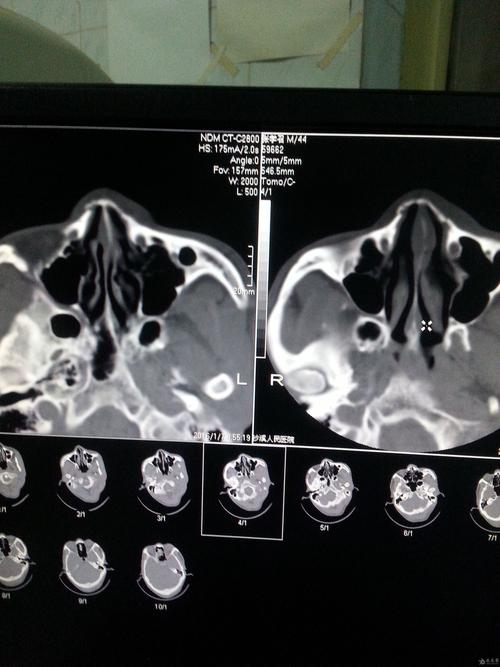

鼻骨骨折片子,鼻骨骨折图片

帮忙看下这个ct片子诊断是鼻骨骨折请问是什么性质的骨折

ct38674:鼻骨骨折吗?

鼻骨骨折ct

鼻骨骨折ct图片